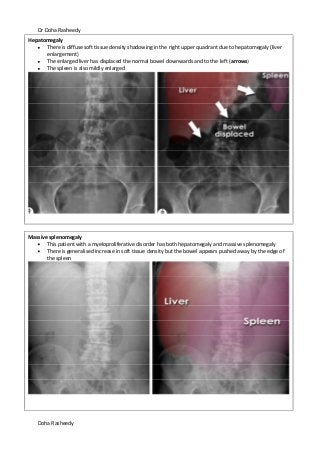

Hepatomegaly

There is diffuse soft tissue density shadowing in the right upper quadrant due to hepatomegaly (liver

enlargement)

The enlarged liver has displaced the normal bowel downwards and to the left (arrows)

The spleen is also mildly enlarged

Massive splenomegaly

This patient with a myeloproliferative disorder has both hepatomegaly and massive splenomegaly

There is generalised increase in soft tissue density but the bowel appears pushed away by the edge of

the spleen